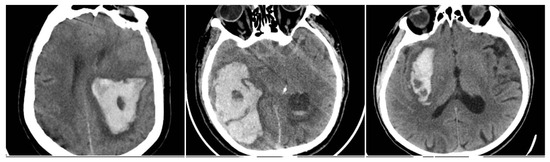

In-hospital mortality analysis demonstrated an even clearer relationship with radiological findings (Figure 7). Patients who died had a mean SUM_BBIS of 1.95, whereas survivors had a mean value of 0.93 (independent-samples t-test p < 0.001). At the individual sign level, all four markers appeared markedly more often in non-survivors: BS in 24.8% vs. 11.1% of survivors (p < 0.001), BHS in 71.0% vs. 15.4% (p < 0.001), IRS in 87.2% vs. 50.8% (p < 0.001), and SS in 52.0% vs. 27.2% (p < 0.001). Table 4 illustrates these proportions. In pairwise comparisons, the Black Hole Sign had the largest absolute gap between fatal and nonfatal cases (50.9 percentage points), suggesting that a large fraction of fatal ICH cases exhibit pronounced intra-hematoma hypodensity indicative of ongoing or repeated bleeding episodes.

Figure 7. Intracerebral hemorrhage from the subgroup with in-hospital mortality, demonstrating a high incidence of NCCT signs. (AC) BHS + IRS + SS. (D) BHS + BS + IRS. (EG) BS + IRS + SS.